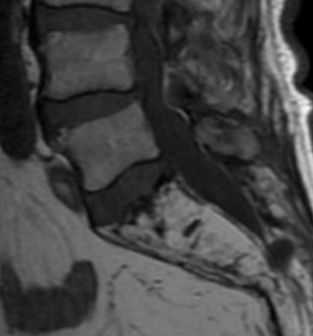

Изменения на МРТ по типу MCh1 характеризуются гипоинтенсивным сигналом на T1-взвешенных изображениях (ВИ), гиперинтенсивным — на Т2-ВИ и изображениях, полученных в Т2 с жироподавлением (T2-FS) или STIR режимах (рис. 1). Интенсивность сигнала увеличивается после введения гадолиния, эти МРТ-признаки соответствуют отеку костного мозга. Результаты микро-компьютерной томографии (микро-КТ) [11] и гистопатологического анализа [2, 12] демонстрируют разрушение и растрескивание КПП, ассоциированное с утолщением костных трабекул и увеличением числа остеобластов и остеокластов, поддерживающих повышенную активность ремоделирования кости. Также выявляется замена нормальной ткани костного мозга на богато васкуляризированную грануляционную ткань.

Рис. 1.ИзменениянаМРТпотипу MCh1. 1 — гипоинтенсивный сигнал на T1-ВИ; 2 — гиперинтенсивный сигнал на Т2-ВИ; 3 — гиперинтенсивный сигнал в режиме с подавлением сигнала от жира (STIR).